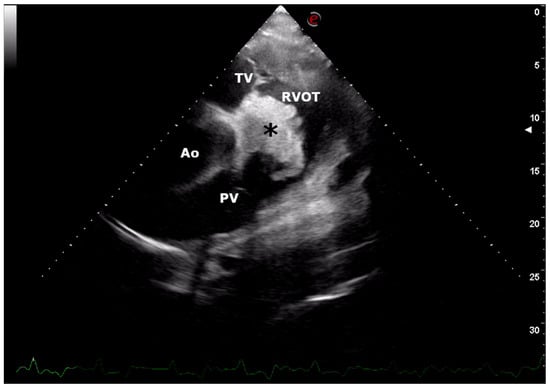

2. Case Presentation